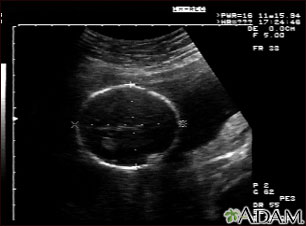

This is a normal fetal ultrasound performed at 19 weeks gestation. Many health care providers like to have fetal measurements to verify the size of the fetus and to look for any abnormalities. This ultrasound is of a head measurement, indicated by the cross hairs and dotted lines.